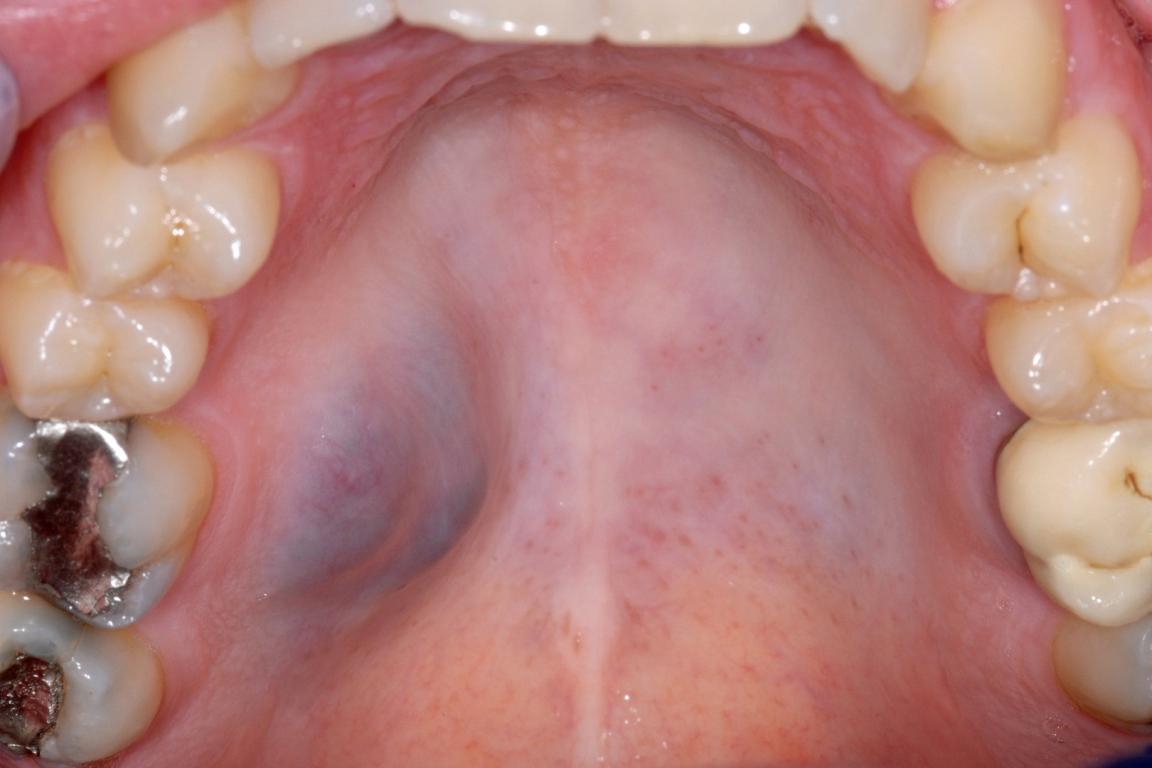

In de mond, en specifiek in het tandvlees, kunnen uiteenlopende afwijkingen voorkomen: van onschuldige veranderingen tot zeldzame, mogelijk levensbedreigende aandoeningen. Sommige afwijkingen komen ook op de huid voor of zijn het gevolg van medicatiegebruik. In deze e-learning leert u veelvoorkomende mondafwijkingen herkennen en onderscheiden op basis van hun klinische presentatie. De cursus is thematisch opgebouwd rond categorieën als witte, wit-rode en rode afwijkingen, pigmentaties, zwellingen en ulceraties. Daarnaast wordt in een apart hoofdstuk stilgestaan bij tandvleesafwijkingen die niet plaque-gerelateerd zijn. Met behulp van bondige teksten en duidelijke klinische afbeeldingen krijgt u inzicht in diagnostiek en classificatie. Ook leert u hoe u patiënten bij wie een mondafwijking wordt vastgesteld, op passende wijze informeert — zowel mondeling als schriftelijk. Deze nascholing helpt u om afwijkingen tijdig te signaleren en professioneel te communiceren over de bevindingen, wat essentieel is voor goede patiëntenzorg.